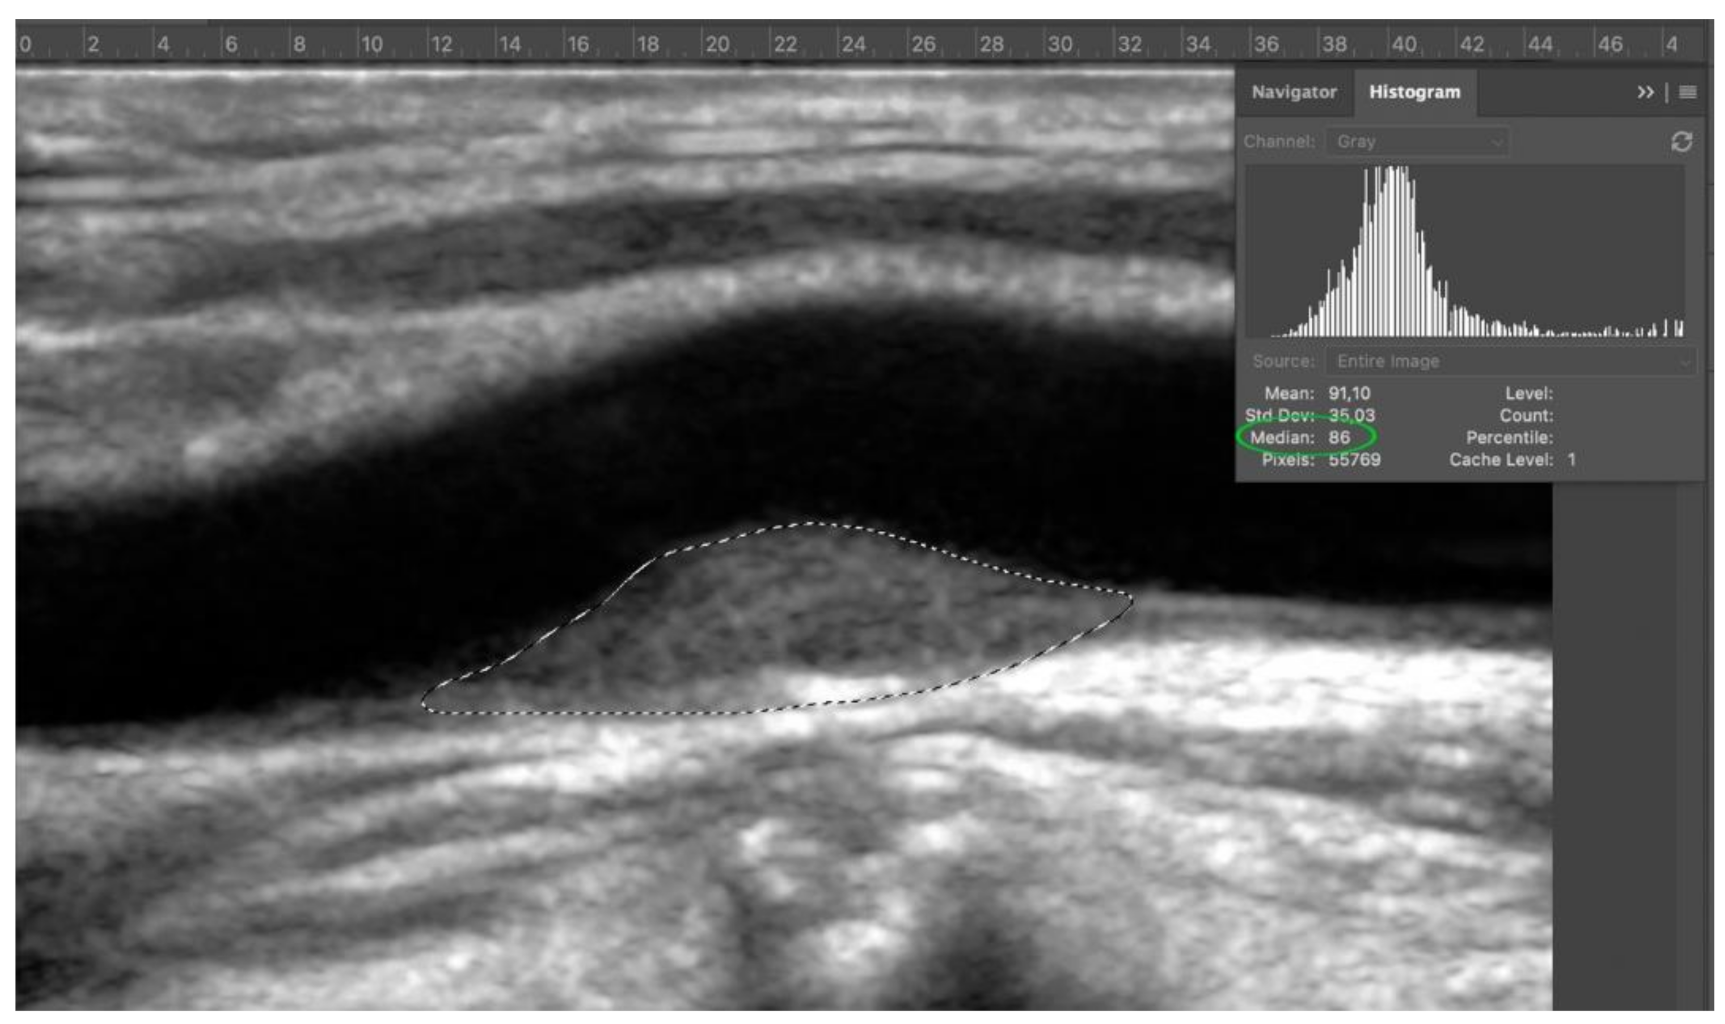

Fourth step: the entire image was normalized via curves with respect to the values previously obtained from normalization of adventitia. The plaque margins were outlined with the lasso tool and the median value showed on histogram was the GSM value (Figure 5).

Figure 5.

Step 4: grey scale median (GSM) of target plaque. In the example, the GSM is 86 (green circle).